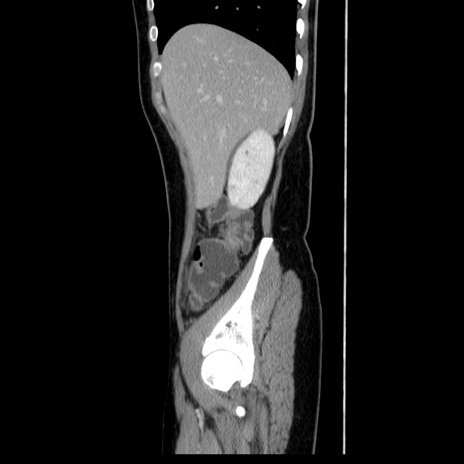

症例39(矢状断像)

【症例】40歳代女性

【主訴】上下腹部痛

【現病歴】2日目から下腹部痛あり。夜間は痛みで眠れなかった。昨日より上腹部痛と下痢が出現。臥位で痛みは軽快したため、休んでいた。本日になって臥位でも立位でも痛みが強くなってきたため救急要請。

【既往歴】子宮内膜症

【身体所見】部:平坦・軟、左上下腹部に圧痛あり、反跳痛あり。

【データ】WBC 21800、CRP 26.78

CT